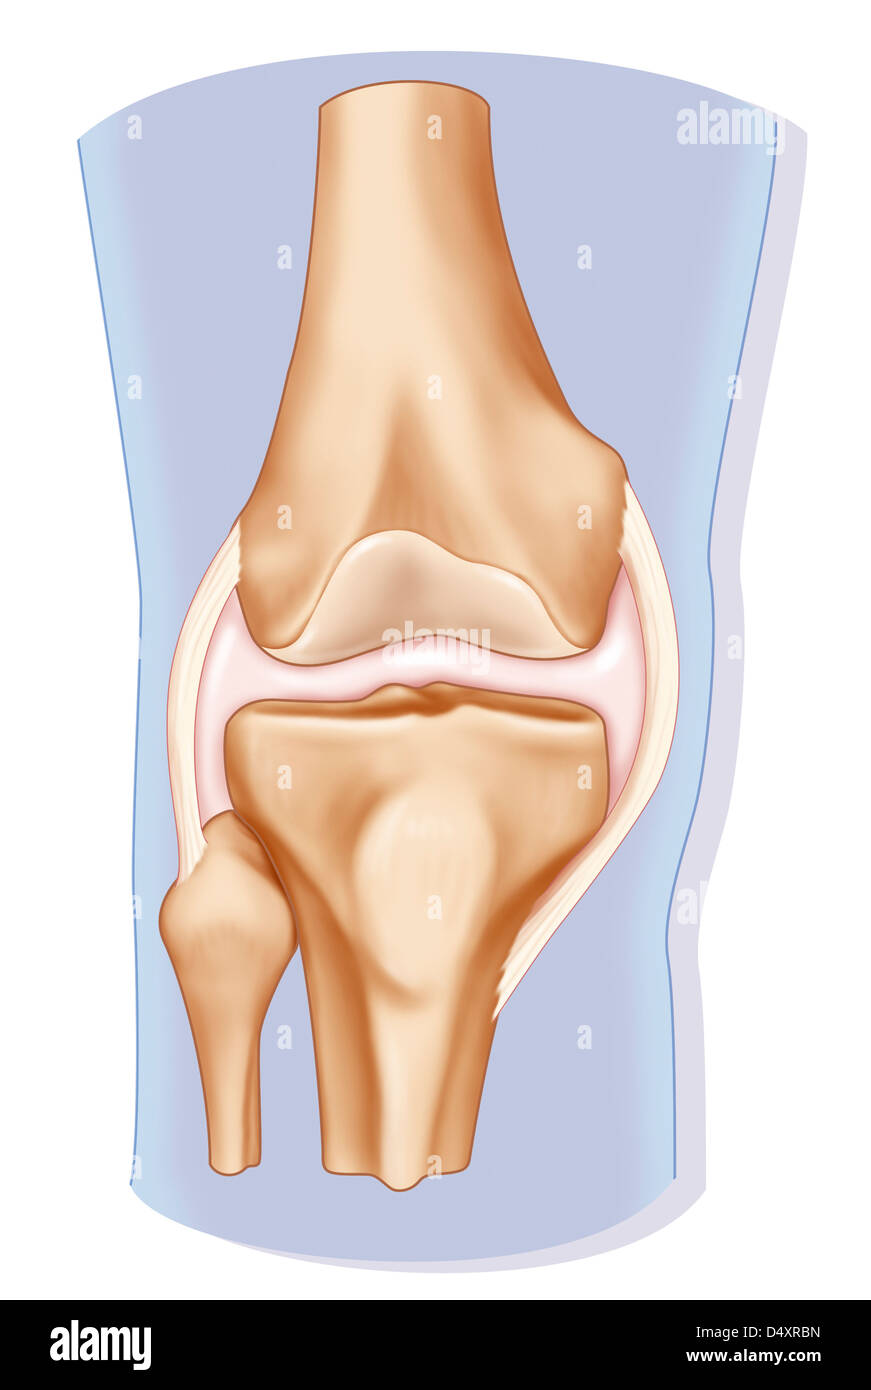

KNEE, DRAWING Stock Photohttps://www.alamy.com/image-license-details/?v=1https://www.alamy.com/stock-photo-knee-drawing-54678841.html

KNEE, DRAWING Stock Photohttps://www.alamy.com/image-license-details/?v=1https://www.alamy.com/stock-photo-knee-drawing-54678841.htmlRMD4XRBN–KNEE, DRAWING